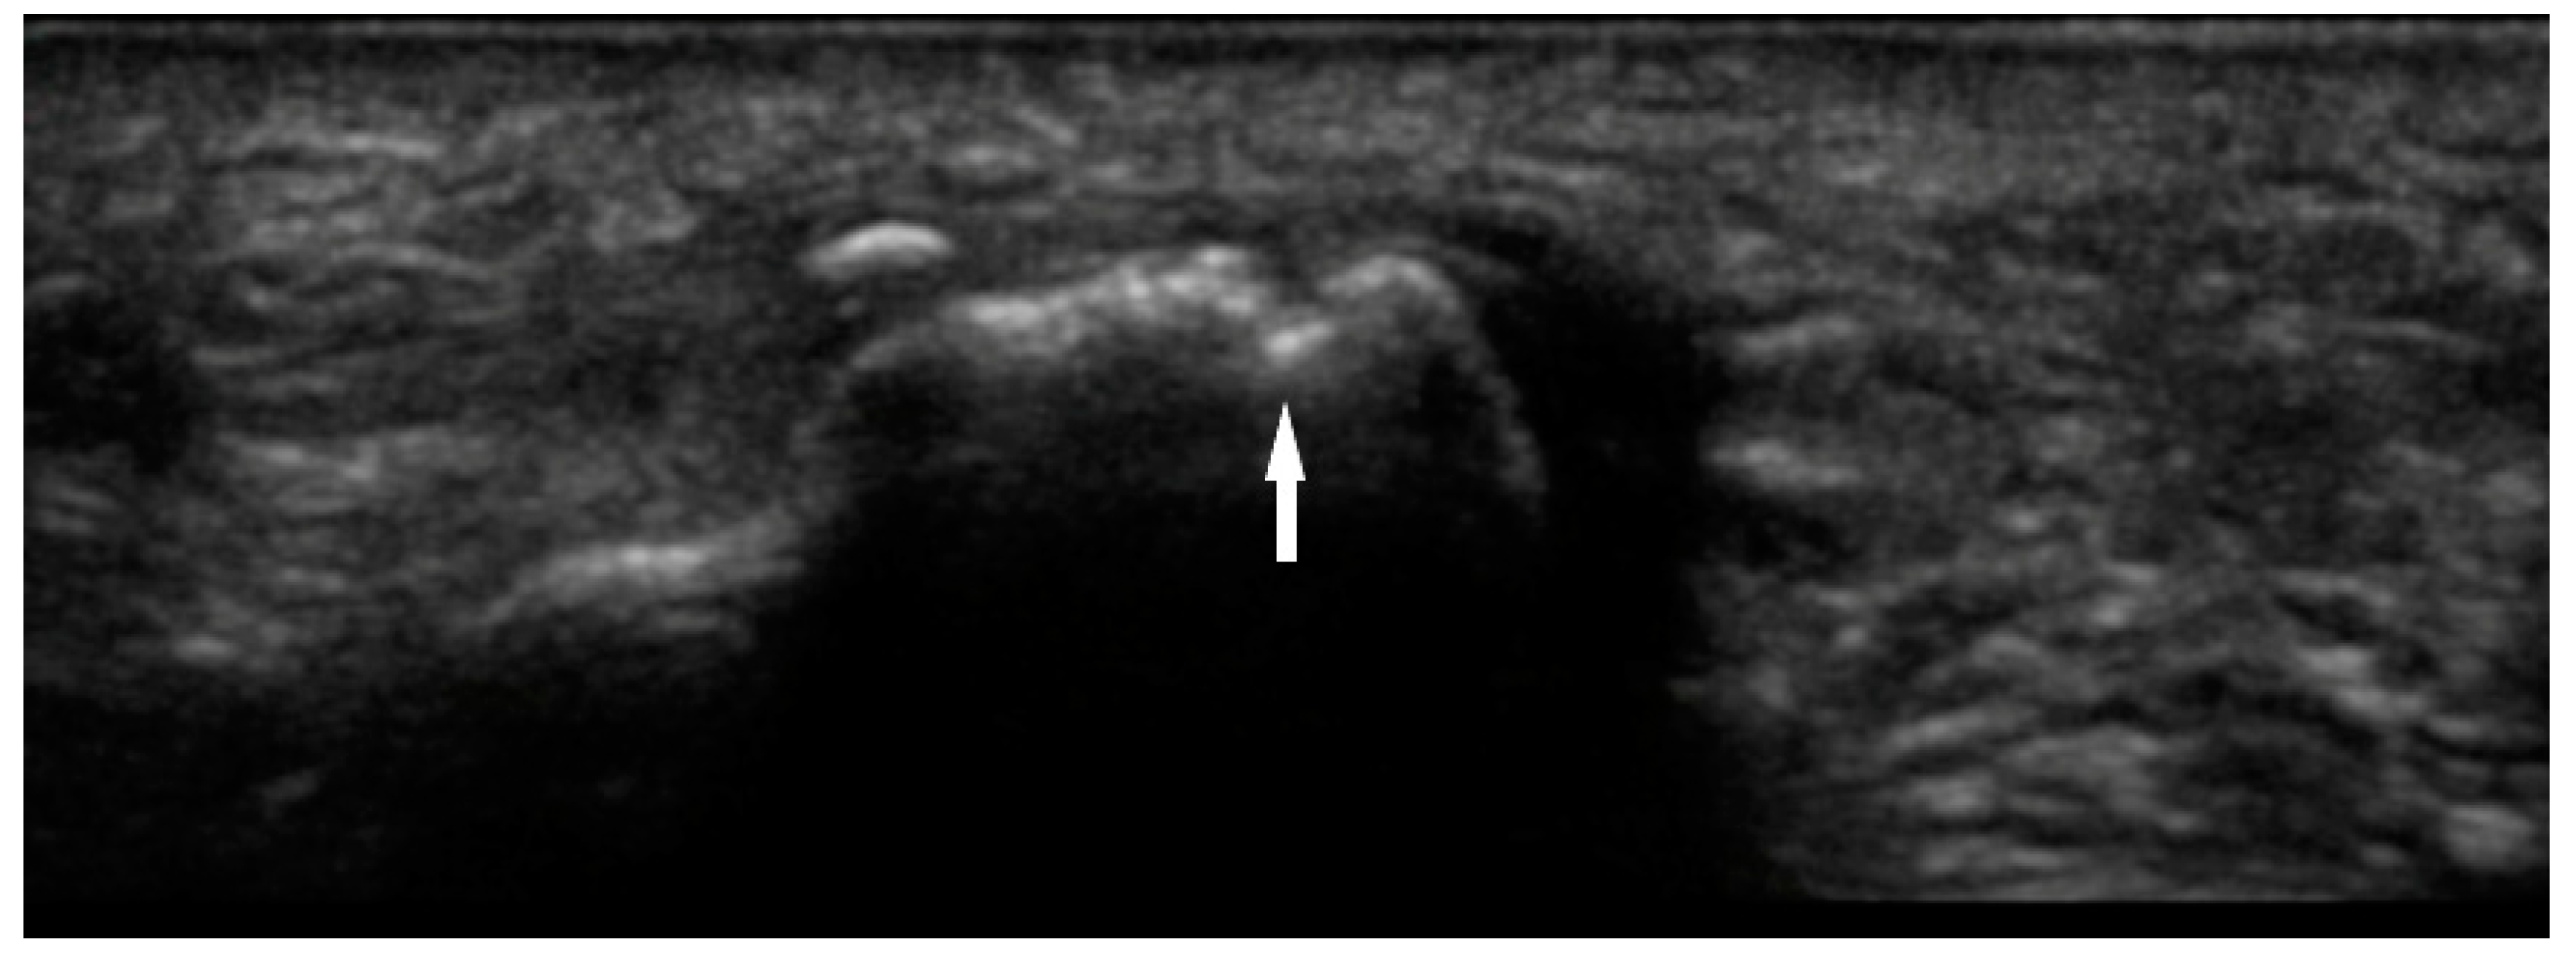

Bone erosions are the result of chronic synovial inflammation, leading to increased periarticular bone resorption. They can be identified on several different imaging modalities, including radiography, MRI, and US. MRI is the most sensitive method of detecting these lesions, but it is not frequently used due to limited accessibility and high cost. While radiography is ubiquitous, it may not be as sensitive as MSUS. Erosions are defined on US as discontinuity of cortical bone identified in two perpendicular or orthogonal planes (Figure 4) [19]. A 2000 study by Wakefield et al. demonstrated that MSUS was more sensitive in evaluation of erosions than radiography. This discrepancy was especially evident in early disease, where sonography detected 6.5 times more lesions in 7.5 times more patients. In late stage of the disease, the difference was 3.4 times and 2.7 times respectively. [10]

Figure 4. Bone erosion of 1st metatarsal phalangeal joint with cortical discontinuity (arrow).